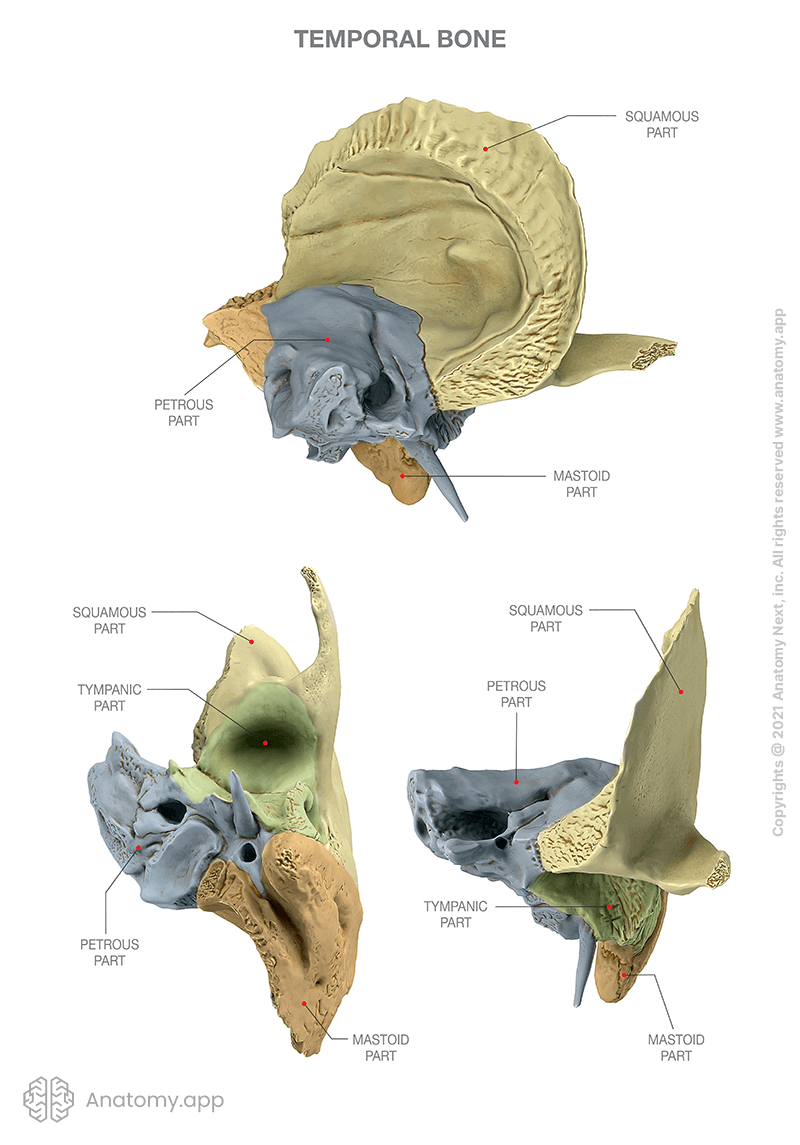

Temporal bone

- Carotid canal

- Ext. acoustic meatus

- Int. acoustic meatus

- CN VII, VIII

- Jugular foramen

- int. jugular v.

- CN IX, X, XI

- Stylomastoid foramen

- Foramen lacerum

- Petrotympanic fissure

- Zygomatic process

- articular eminence

相鄰骨

Pr, O, S, M